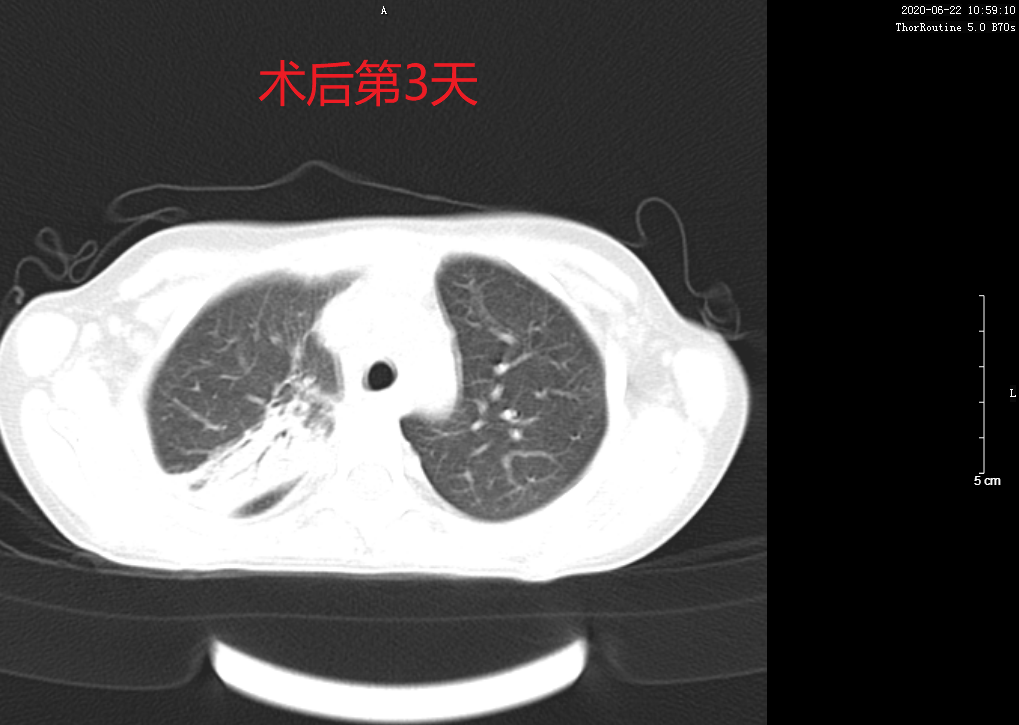

本次支气管镜术在PICU(儿童重症监护室)内密切监护的条件下,进行局麻镇静,使患儿安静睡眠后行支气管镜检查,支气管镜经右鼻腔进入肺部进行治疗,整个操作过程顺利,患儿无不良反应,病情平稳。术后两天患儿咳嗽症状消失,第3天复查胸部CT病灶较前明显吸收,疗效显著。

术后患儿胸部CT